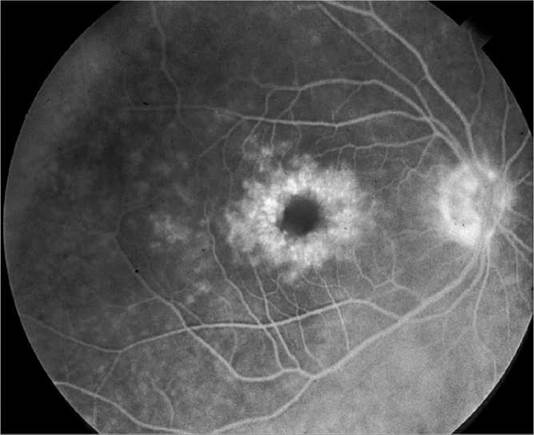

Critical. One or more discrete near-translucent or light gray vitreous opacities, one often in the shape of a ring (“Weiss ring”) or broken ring, suspended over the optic disc (see Figure 11.1.1) .

FIGURE 11.1.1 Posterior vitreous detachment.